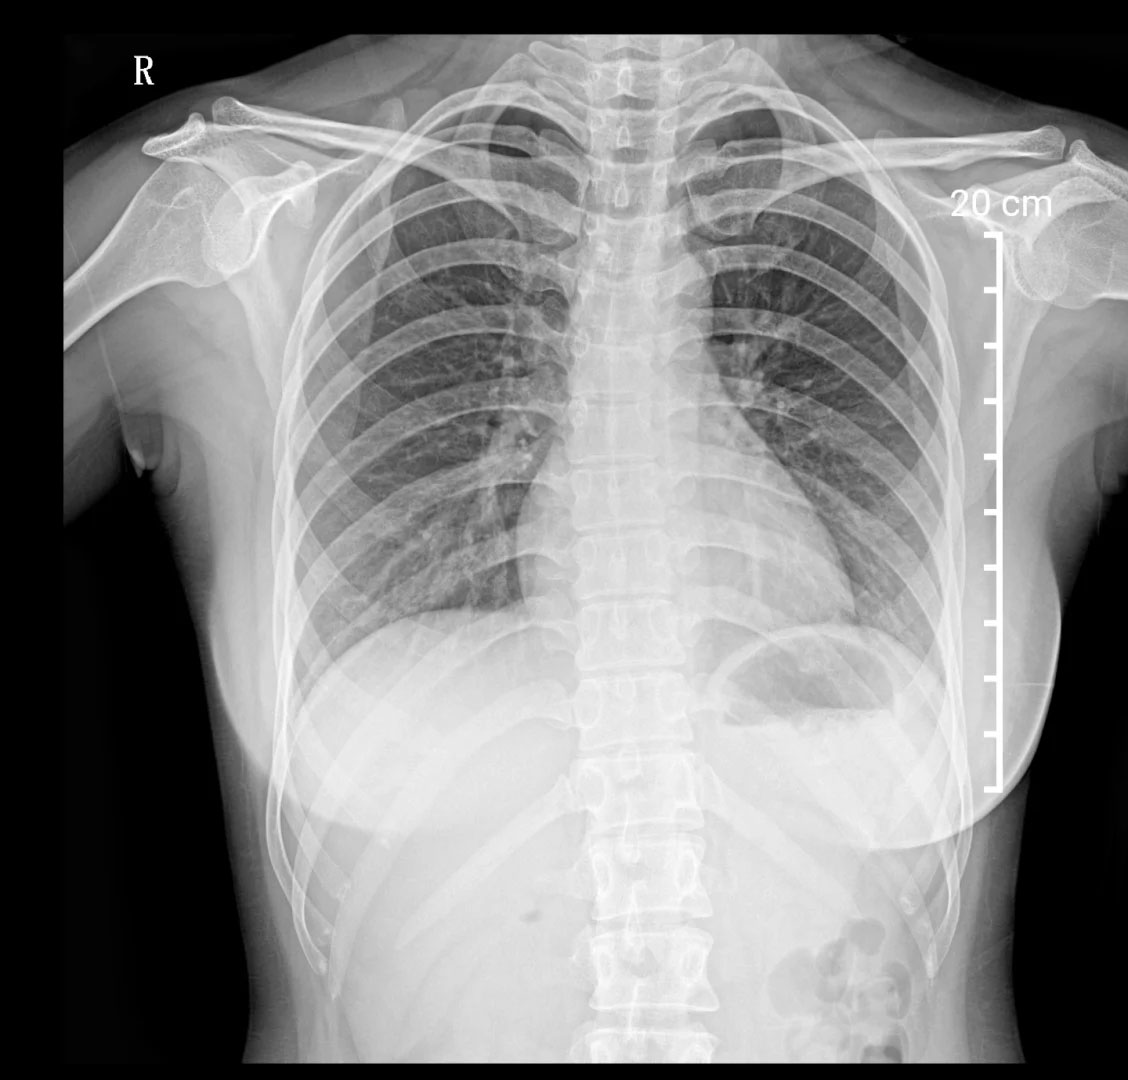

胸部X光檢查,建筑工地的環(huán)境復(fù)雜,肺部檢查很重要。有的工種需要長(zhǎng)期接觸灰塵,可能會(huì)引起輕微肺部炎癥。在工地工作的時(shí)候,盡量要佩戴好口罩。